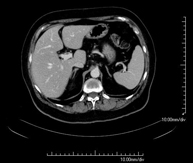

Prova diagnòstica que consisteix en l'estudi de l'abdomen d'alta definició anatòmica (fetge, vesícula biliar, via biliar, pàncrees, melsa, estómac, intestins, ronyons, estructures vasculars, bufeta, úter i ovaris, etc.) mitjançant l'ús d'un equip de TC (Tomografia Computeritzada). Aquestes imatges s'estudien posteriorment en una estació de treball que permet obtenir reconstruccions bidimensionals en diferents plànols de l'espai i també reconstruccions 3D (volumètriques). La majoria d'estudis requereixen l'ús de contrast iodat per millorar la definició de les imatges. - TC Pelvis

Prova diagnòstica que consisteix en obtenir imatges bi i tridimensionals de l'abdomen d'alta definició anatòmica (estructures òssies, estructures vasculars, fetge, pàncrees, vesícula biliar, ronyons, glàndules suprarenals, melsa, intestí prim i gros, bufeta, úter i ovaris, pròstata i vesícules seminals, urèters, etc.) mitjançant l'ús d'un equip de TC (Tomografia Computeritzada). La majoria d'estudis requereixen l'ús de contrast iodat. - TC Fetge

Prueba diagnóstica que consiste en obtener imágenes del abdomen de alta definición anatómica (hígado, vesícula biliar, vía biliar, páncreas, bazo, estómago, intestinos, riñones, estructuras vasculares, vejiga, útero y ovarios, etc.) mediante el empleo de un equipo de TC (Tomografía Computarizada). Dichas imágenes se estudian posteriormente en una estación de trabajo que permite reconstrucciones bidimensionales en diferentes planos del espacio, y también reconstrucciones 3D (volumétricas). La mayoría de estudios requieren el empleo de contraste yodado para mejorar la definición de las imágenes. - TC Estudio rotacional EEII